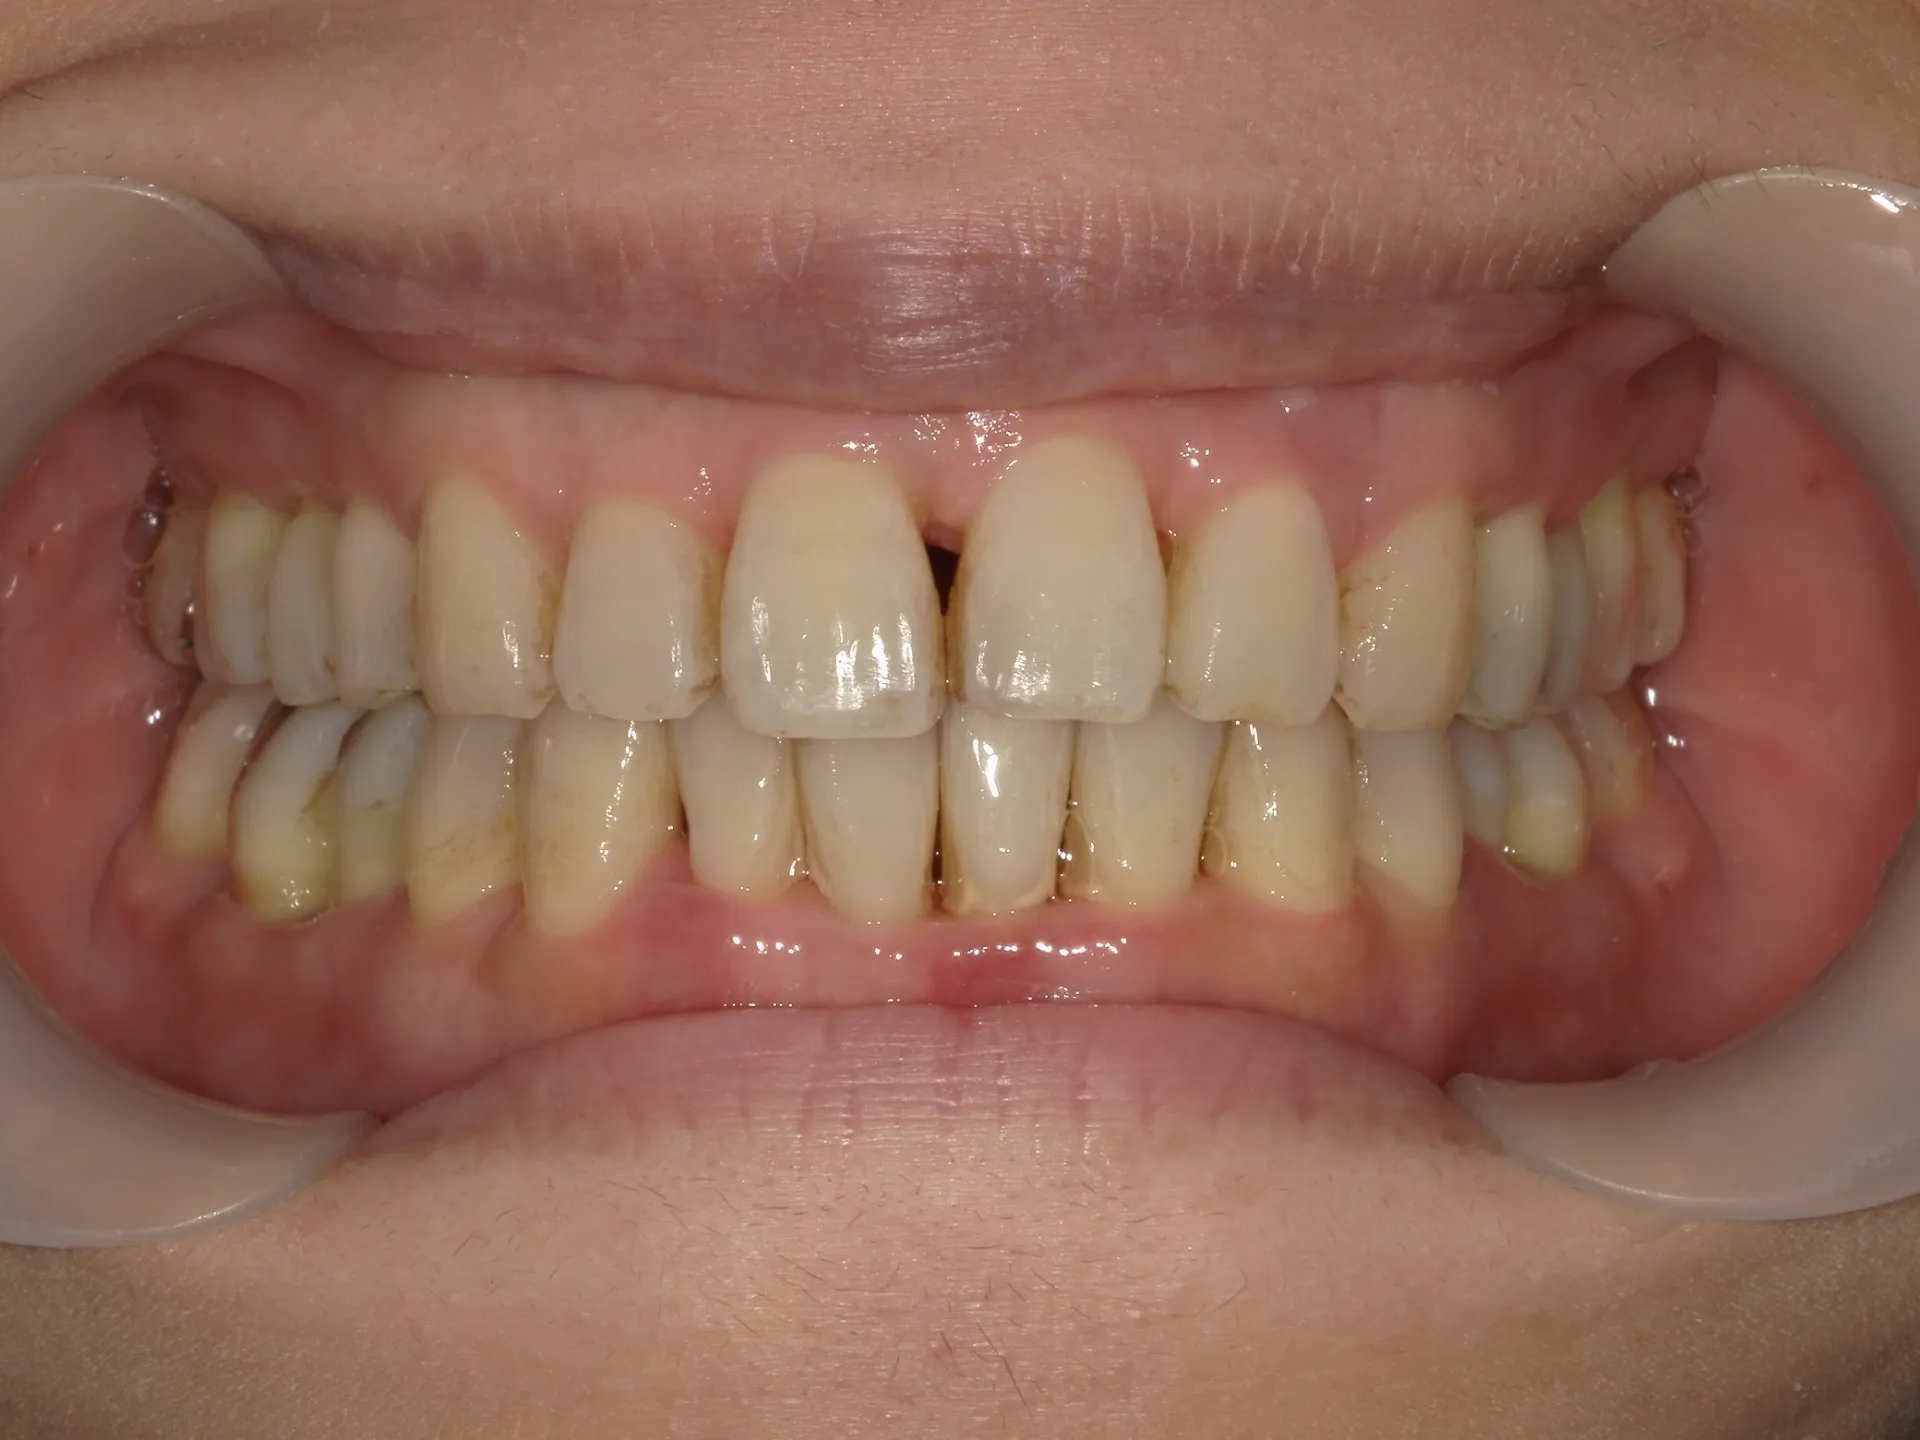

当院では矯正治療と歯周治療を平行して行うことにより矯正治療を進めていけることができました。

しかしながら、今回の治療途中で歯茎が腫れるなどの影響もあり、歯周治療中の矯正治療はリスクであることは患者様にも初回の段階で説明していることもあり、患者様もこの状態の歯並びで満足しており、歯を残すためにも今回は矯正治療を中断する希望をされました。